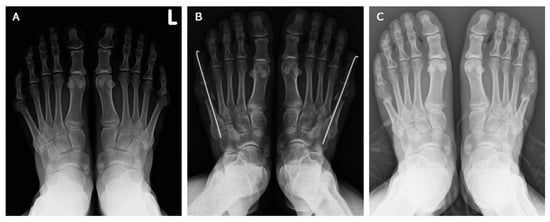

Symptomatic Bunionette Treated with Sliding Oblique Metatarsal Osteotomy—Case Series

2.2. Operative Technique and Postoperative Care